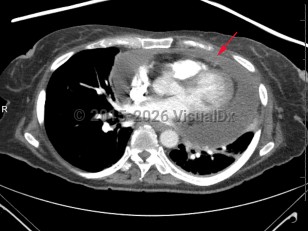

- Large bore intravenous (IV) access

- Point of care ultrasound assessment

- IV fluid administration

- Inotropic support

- Analgesia

- Pericardiocentesis